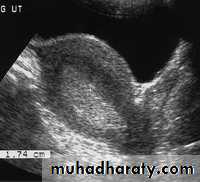

• Pathology of Endometrium

Endometrial hyperplasia. US image shows an endometrium with diffuse thickening (maximum thickness, 1.74 cm) due to hyperplasia (cursors). This finding was confirmed at biopsy.